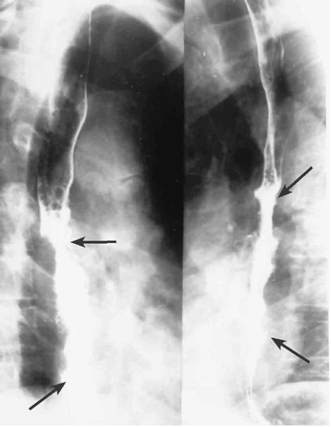

- צילומי הוושט, לאחר בליעת בריום: בצילומי הוושט ניתן לראות פגם מילוי, כיבים, אי-סדירות של הרירית, היצרויות, הפרעות בגל הניע (פריסטלטיקה) והרחבת הוושט מעל החסימה (תצלומים 15.1-17.1)